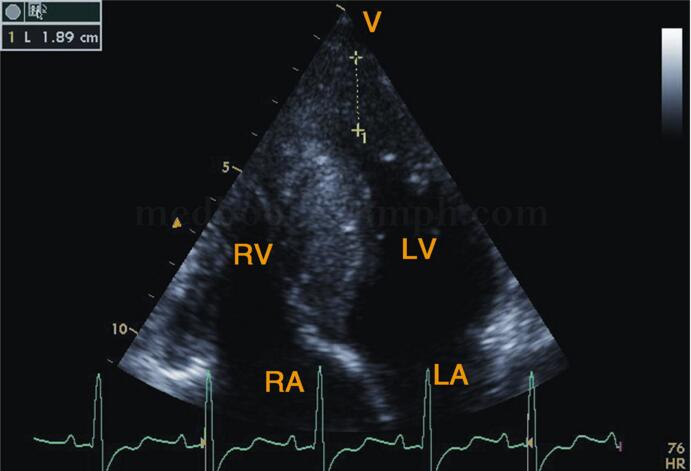

(4)心尖肥厚型心肌病:心室和(或)心尖部心腔明显狭小,呈“核桃样”改变(图2‐1‐200),严重者心尖部心腔闭塞(图2‐1‐201)。CDFI示LVOT内血流速度一般正常。

图2‐1‐200 心尖四腔心切面心尖部心肌明显增厚,心腔明显狭小,呈“核桃”状